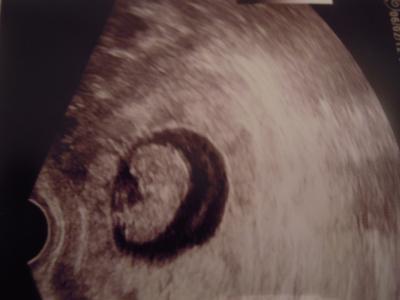

Hallo.Ich habe gerade mal mein letztes Ultraschallbild abfotografiert,weil ich ja noch gar kein Bild gezeigt habe.Da war ich 9+4 wo ich das letzte mal beim Fa war. Ich hab dann mal die Bilder von den anderen mit meinem verglichen und meins sieht eher wie eine kleine Bohne aus.Und bei den anderen wie Gummibärchen.Aber vielleicht weil meins von der Seite ist,sieht man aber ganz gut glaub ich.Obwohl meine Fa nicht das neueste Ultraschallgerät hat. Lg ana mit Bauchbohne

Bild zu Meine Bauchbohne - Forum für September - Mamis